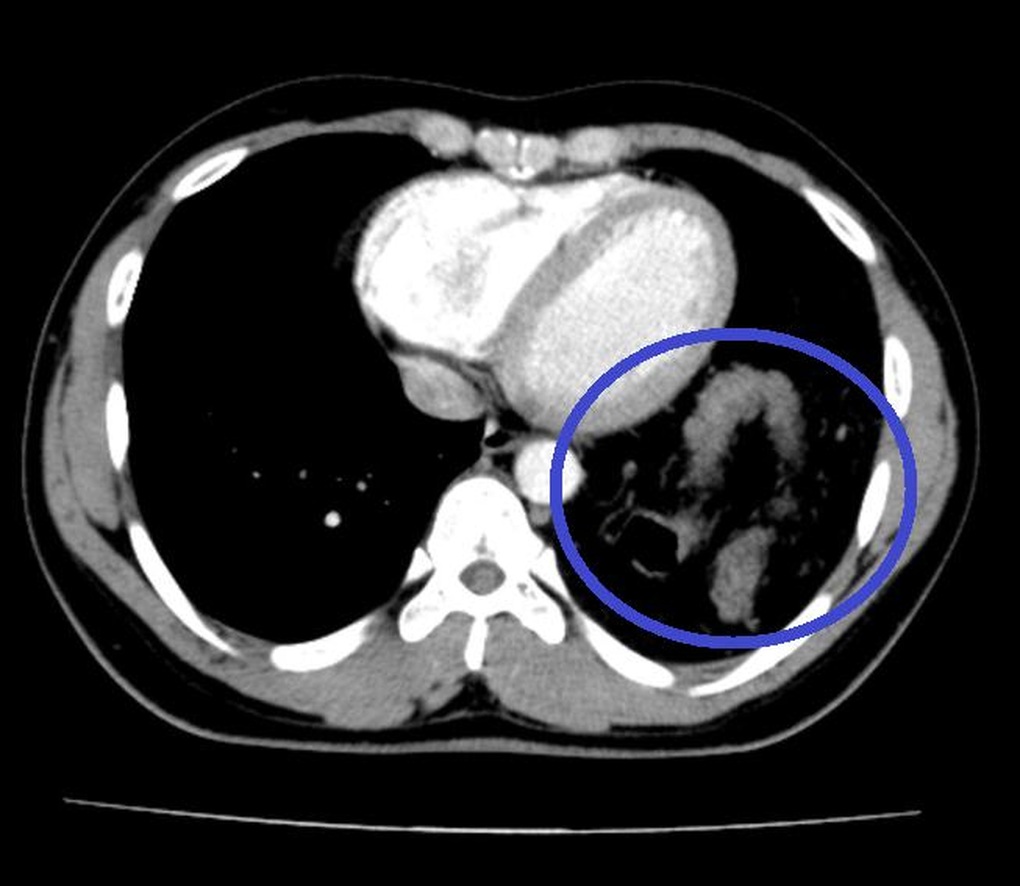

Hình ảnh chụp cắt lớp vi tính phát hiện đại tràng chui lên ngực trái bệnh nhân.

Kết quả chụp X-quang khiến bác sĩ bất ngờ, khi phát hiện có tình trạng có hình bóng hơi của ruột ở trên ngực trái. Sau khi làm thêm một số xét nghiệm, chiếu chụp, hội chẩn liên khoa, bệnh nhân được chẩn đoán có thoát vị tạng bụng qua cơ hoành lên ngực trái, được chuyển tới Khoa Phẫu thuật Tiêu hóa - Gan mật tụy để tiến hành phẫu thuật.

BS Du cho biết, khi tiến hành mổ nội soi, vừa đưa máy soi vào ổ bụng các bác sĩ đã thấy gần toàn bộ đại tràng ngang, lách, dạ dày và mạc nối lớn đã chui qua cơ hoành lên khoang màng phổi bên trái.